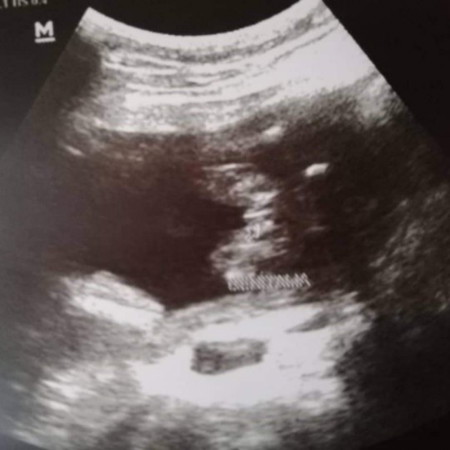

Hello. 7months na ko. Hindi pa din malaman kung boy or girl. Probable female palang. ? Nasa breach position kasi si baby. Tapos nakita sa cas malaki sa normal na sukat ng ulo ng baby ung sa baby ko. ? Monthly imomonitor kng lalaki pa dn ung head nya. Kung hindi possible cs ako. At ichecheck kng may tubig sa ulo si baby. At pag ngyari un tutubuhan daw siya sa ulo pagka labas nya. Hays. ? Help me mga mamsh. Pls. Include my baby sa prayers nyo. Pleaseee. Thank you.